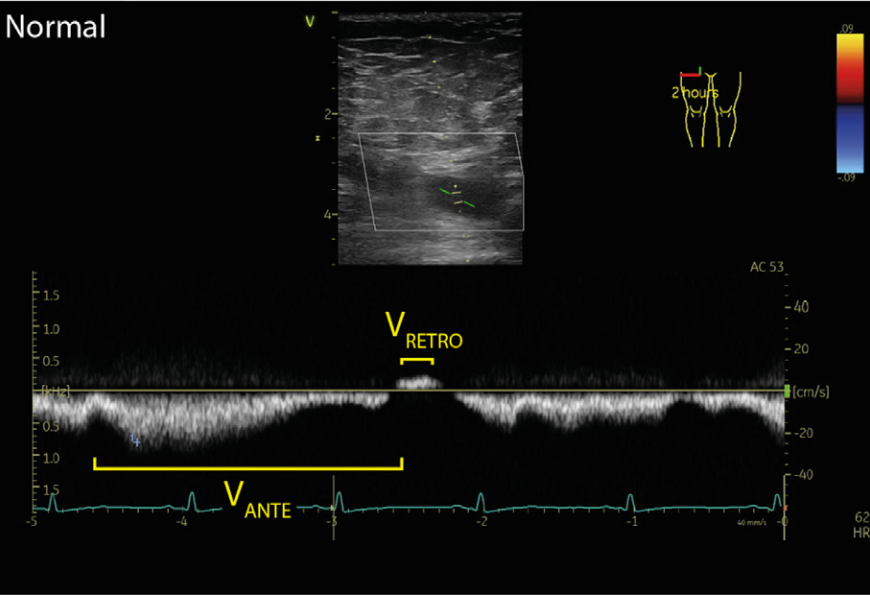

Normal femoral vein flow Doppler for comparison. Note the respiratory modulation and wide monophasic negative vein flow velocity representing antegrade vein flow with minor retrograde vein flow components.

Antegrade femoral vein flow velocity representing vein flow from the periphery to the right side of the heart is 30 cm/s, whereas retrograde velocity of 35 cm/s represents systolic flow reversal, right ventricular dysfunction

Femoral vein Doppler pulsatility in venous congestion Serial femoral vein Doppler in a patient with severe venous congestion, and after 4 days of diuresis 1 . Femoral vein flow is biphasic with an important retrograde component